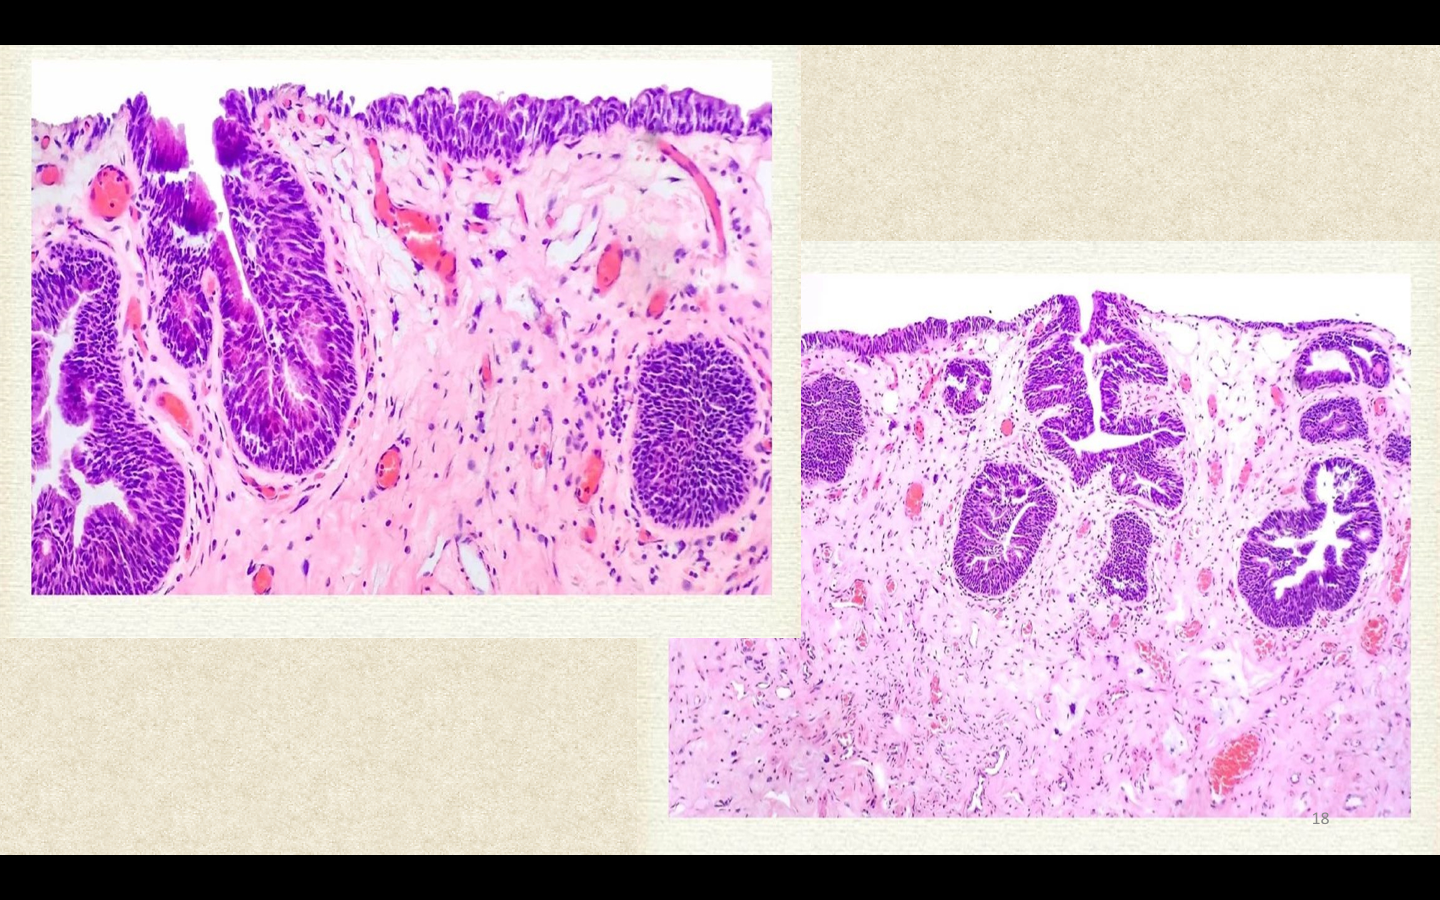

肾单位(nephron)是肾脏的基本结构和功能单位,由肾小球和其下属的近端肾小管、髓袢、远端肾小管组成。其中肾小球的结构和功能最复杂,通过毛细血管袢的过滤形成原尿,原尿流经肾小管时,通过吸收和浓缩,将原尿改造为终尿。肾小球(glomerulus)由两部分构成,即位于中央的血管球和位于周围的肾小囊。肾小囊(renal capsule or Bowman’s capsule)是肾小管盲端凹陷而成的双层囊,两层间的狭腔称为肾小囊腔(urinary space)。肾小囊的外层由单层扁平上皮构成,在肾小球尿极处与近端肾小管上皮相连。在血管极处,外层细胞反折延续成肾小囊内层,紧包在成簇的毛细血管袢的外面。血管球是一团蟠曲成球状的毛细血管。一条入球小动脉由血管极处进入肾小球后反复分支形成互相吻合的毛细血管袢,最后又在血管极处汇成一条出球小动脉

电镜观察,肾小球毛细血管壁有三层结构,中间为基底膜,内侧衬以内皮细胞(endothelium),外侧被以上皮细胞(epithelium),即肾小囊内层上皮细胞。毛细血管袢之间有支持毛细血管的系膜(mesangium)。系膜区域有系膜细胞(mesangial cell)和系膜基质(mesangial matrix)充填在各叶毛细血管之间,构成毛细血管袢的轴心,在正常3μm的切片下,一个系膜区有1~2个系膜细胞。系膜基质是系膜细胞的产物,结构与基底膜致密层相似,但电子密度稍低。

肾小囊内层上皮细胞就是通常所说的肾小球上皮细胞,又称足细胞(podocyte),其形态特殊,胞体的一部分伸出并形成足状突起,紧贴在基底膜外侧。足突和足突之间有一裂隙,宽约25nm,称为裂孔(slit pore),裂孔上有厚约4~6nm的膜,称为裂孔膜(slit membrane)。裂孔膜实际上是足细胞单位膜最外面的一层。许多疾病状态下,足突相互融合,裂孔消失。基底膜(glomerular basement membrane)由三层构成,中间一层电子密度高,称致密层;内外两侧电子密度低,分别称为内、外疏松层。急速冷冻深度蚀刻电镜技术观察表明,基底膜致密层是由细纤维构成的网状构造,与上皮细胞和内皮细胞之间由垂直的架桥细纤维连接。